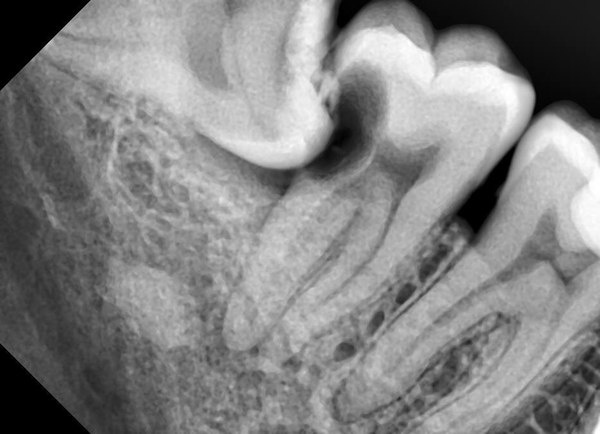

4- «лежит» упершись в другой зуб. Тут есть факт давления на зубы и возможность искривления зубного ряда, но кроме этого более неприятное так это то, что может привести разрушению впереди стоящего зуба (седьмого. А они то нам нужны). При этом зуб может быть как прорезавшийся, так и лежать в кости. И снова дяденька хирург придёт на помощь и удалит подлеца.

Вот и нет кусочка 7го.

Восьмёрка в кости "сожрала" корень.